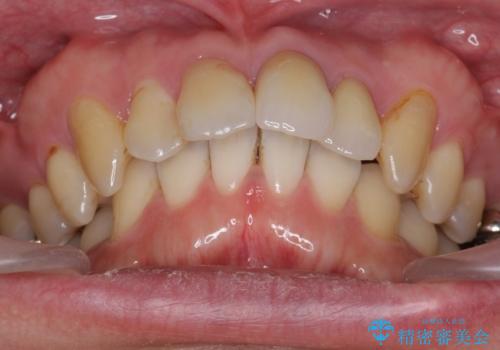

出っ歯を部分矯正で目立たなくする セラミック治療も

- 前歯の突出を主訴に来院。

全体矯正を行うとなると健康な歯を4本抜歯することになるため、歯は抜かず上だけの部分矯正で最小限で前歯を整えることにしました。

前歯は少し細く削って前に出ないように整えました。

左上の1番目の前歯は神経を取ってある歯でした。今後変色もすすんでいくため、治療のやり直しを行いセラミックでかぶせました。